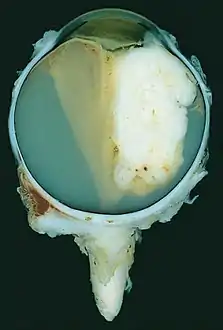

A pathology specimen of a retinoblastoma tumor from an enucleated eye of a 3-year-old female